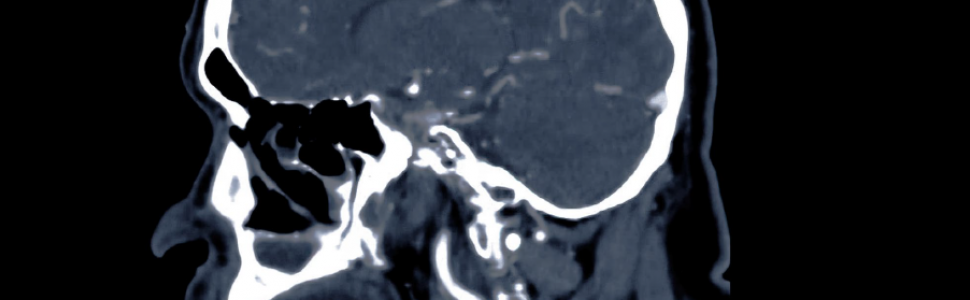

W tomografii stożkowej (cone beam computed tomography – CBCT) wiązka promieniowania w kształcie stożka (stąd nazwa) jest używana do wygenerowania kilkuset zdjęć rentgenowskich podczas obrotu lampy rentgenowskiej wokół głowy pacjenta w zakresie 180 lub 360 stopni. Inna nazwa tej przekrojowej techniki obrazowania to cyfrowa tomografia wolumetryczna, inaczej objętościowa (digital volumetric tomography – DVT lub digital volumetric imaging – DVI). Nazwa ta również ma swoje uzasadnienie, gdyż podczas badania rejestrowana jest pewna objętość danych, w przeciwieństwie do tomografii komputerowej (TK), w której obrazowany jest pełen zakres między wyznaczonymi poziomami górnym i dolnym.